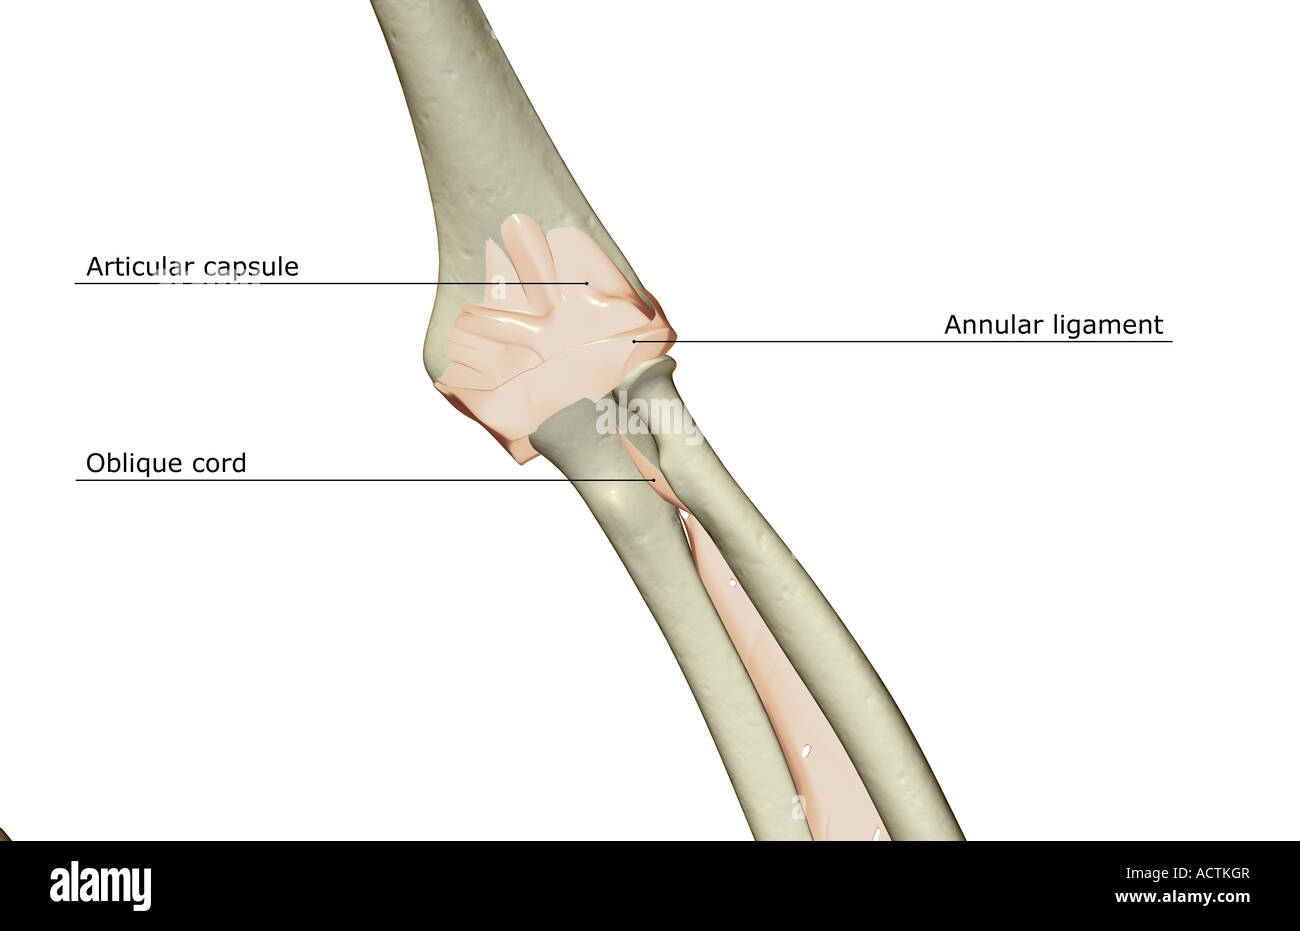

Ligaments of the elbow joint Stock Photohttps://www.alamy.com/image-license-details/?v=1https://www.alamy.com/stock-photo-ligaments-of-the-elbow-joint-13227958.html

Ligaments of the elbow joint Stock Photohttps://www.alamy.com/image-license-details/?v=1https://www.alamy.com/stock-photo-ligaments-of-the-elbow-joint-13227958.htmlRFACTKGR–Ligaments of the elbow joint